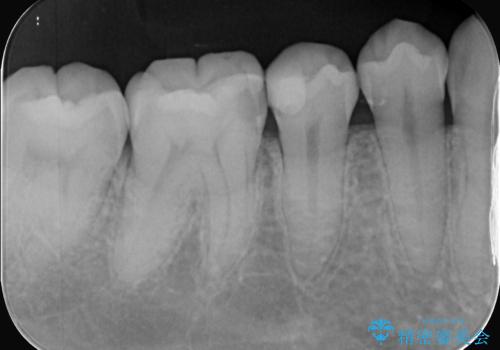

- 主訴:右下の奥歯がたまに冷たい物や甘いものでしみる

右下6番目の歯に大きめのう蝕を認め、形態の再現性を考えインレーでの治療となりました。

右下6の近心にう蝕が認められう蝕の範囲が大きかったため、歯冠形態の再現性の高いインレーでの修復とし、材質は審美性、清掃性に優れたセラミックを選択しました。